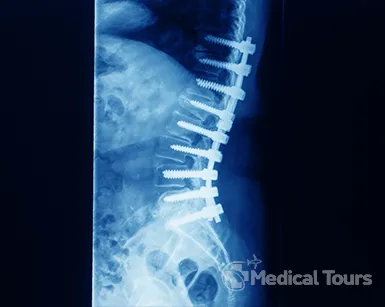

Spinal Fusion Surgery

What is Spinal Fusion Surgery?

Human beings are vertebrates and the spinal record, that remains within the long vertebral column comprises of one of the most important parts of the nervous system. Sometimes physicians and health care experts join two or more adjacent vertebral bones to form one solid and single bone through a surgery. This surgery is known as spinal fusion surgery of the vertebral column. The other names of the spinal fusion surgery are as follows:

There are three basic types of spinal fusion. The classification of spinal fusion largely depends on the type of method used for the surgery and the bones that are fused during the surgery. The three basic types of spinal fusion surgery are listed here as follows:

• Cervical fusion: Vertebral bone in the neck region.

• Thoracic fusion: Vertebral bone in the mid-back portion.

• Lumbar fusion: Vertebral bone in the lower back area.